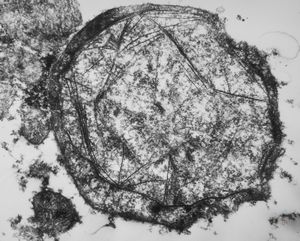

M,26y. | ribosome-lamella bodies in adenocarcinoma

M,41y. | ribosome-lamella complex in tricholeukocyte -hairy cell leukemia, spleen

M,41y. | ribosome-lamella complex in tricholeukocyte -hairy cell leukemia, spleen

M,41y. | ribosome-lamella complex in tricholeukocyte -hairy cell leukemia, spleen